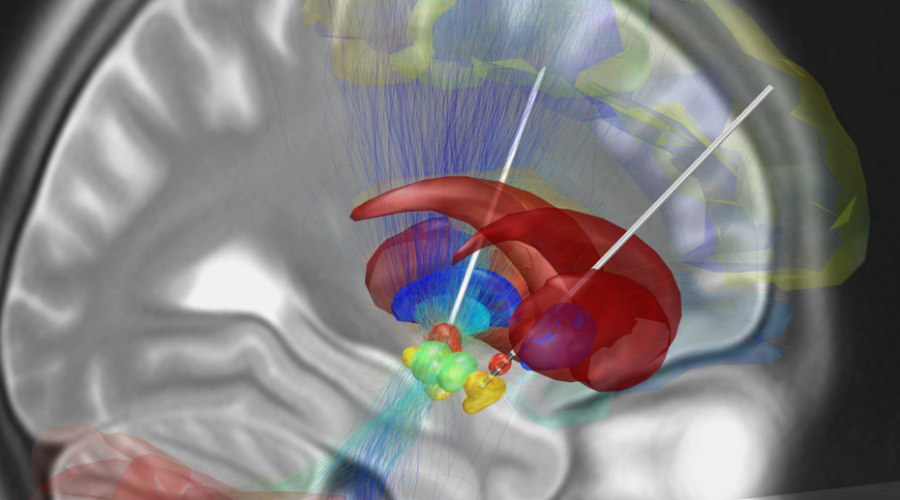

Anche gli avveniristici supporti robotici, lodati dalle recensioni mediche, sono diventati una realtà. Questi complessi apparecchi consentono una precisione di operazione altrimenti inarrivabile, bypassando i limiti fisici del personale umano, come la stanchezza e i movimenti involontari delle mani. Importantissimo anche il supporto dei neuronavigatori, in grado di ricostruire nel dettaglio su monitor l’immagine delle aree da trattare con gli strumenti da parte del neurochirurgo.

Per quel che concerne la diagnostica, il ‘mapping’ del cervello si può ottenere tramite lo scarico di piccole quantità di elettricità lungo il cranio, operazione capace di evidenziare le aree di maggiore attività neuronale. Una fusione di elettronica, robotica e medicina che si è valsa il plauso delle opinioni e delle recensioni positive da parte della comunità medica e scientifica internazionale. Veri e propri gioielli della tecnologia indicati come il futuro della medicina di precisione dala Clinica Villa Mafalda e dal suo reparto oculistico high tech AktiVision dotato di strumentazione di diagnostica di altissima qualità capace di risalire dal monitoraggio dell’area oculare a patologie neurologiche e di natura cerebrale come la sclerosi multipla. Maggiori info su AktiVision le trovi nel portale della Clinica Villa Mafalda legato al reparto oculistico.